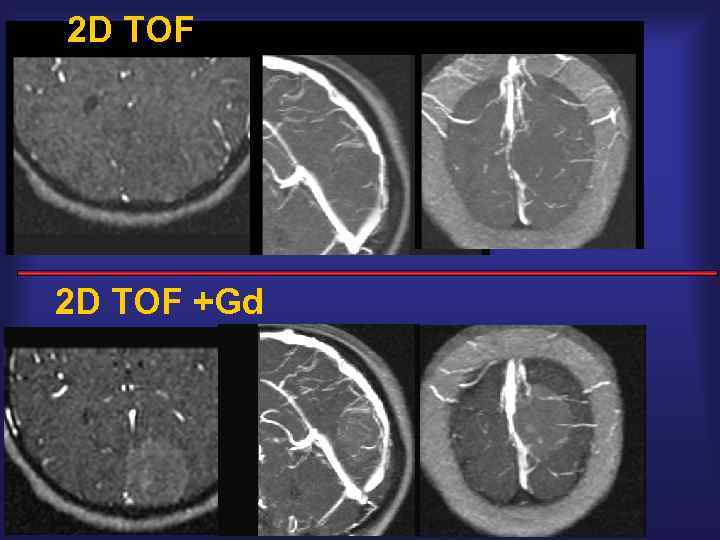

2 D TOF +Gd